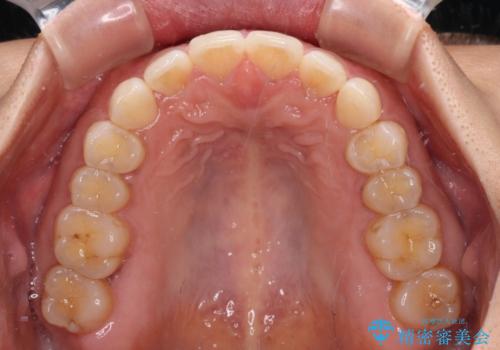

【モニター】前歯のすきっ歯をインビザラインで改善

- 上顎前歯の隙間と口元の突出感を気にして来院された患者様です。

高校生の時に行った矯正治療の後戻りであり、歯列不正は軽度であったので、インビザラインにて治療を行うこととしました。

すきっ歯はあっという間に後戻りを起こすので、可及的に後戻りを防止するために、上下前歯部を舌側からワイヤーで固定しています。

通常は下顎前歯のみに行っていますが、空隙歯列弓では上顎でも行っています。